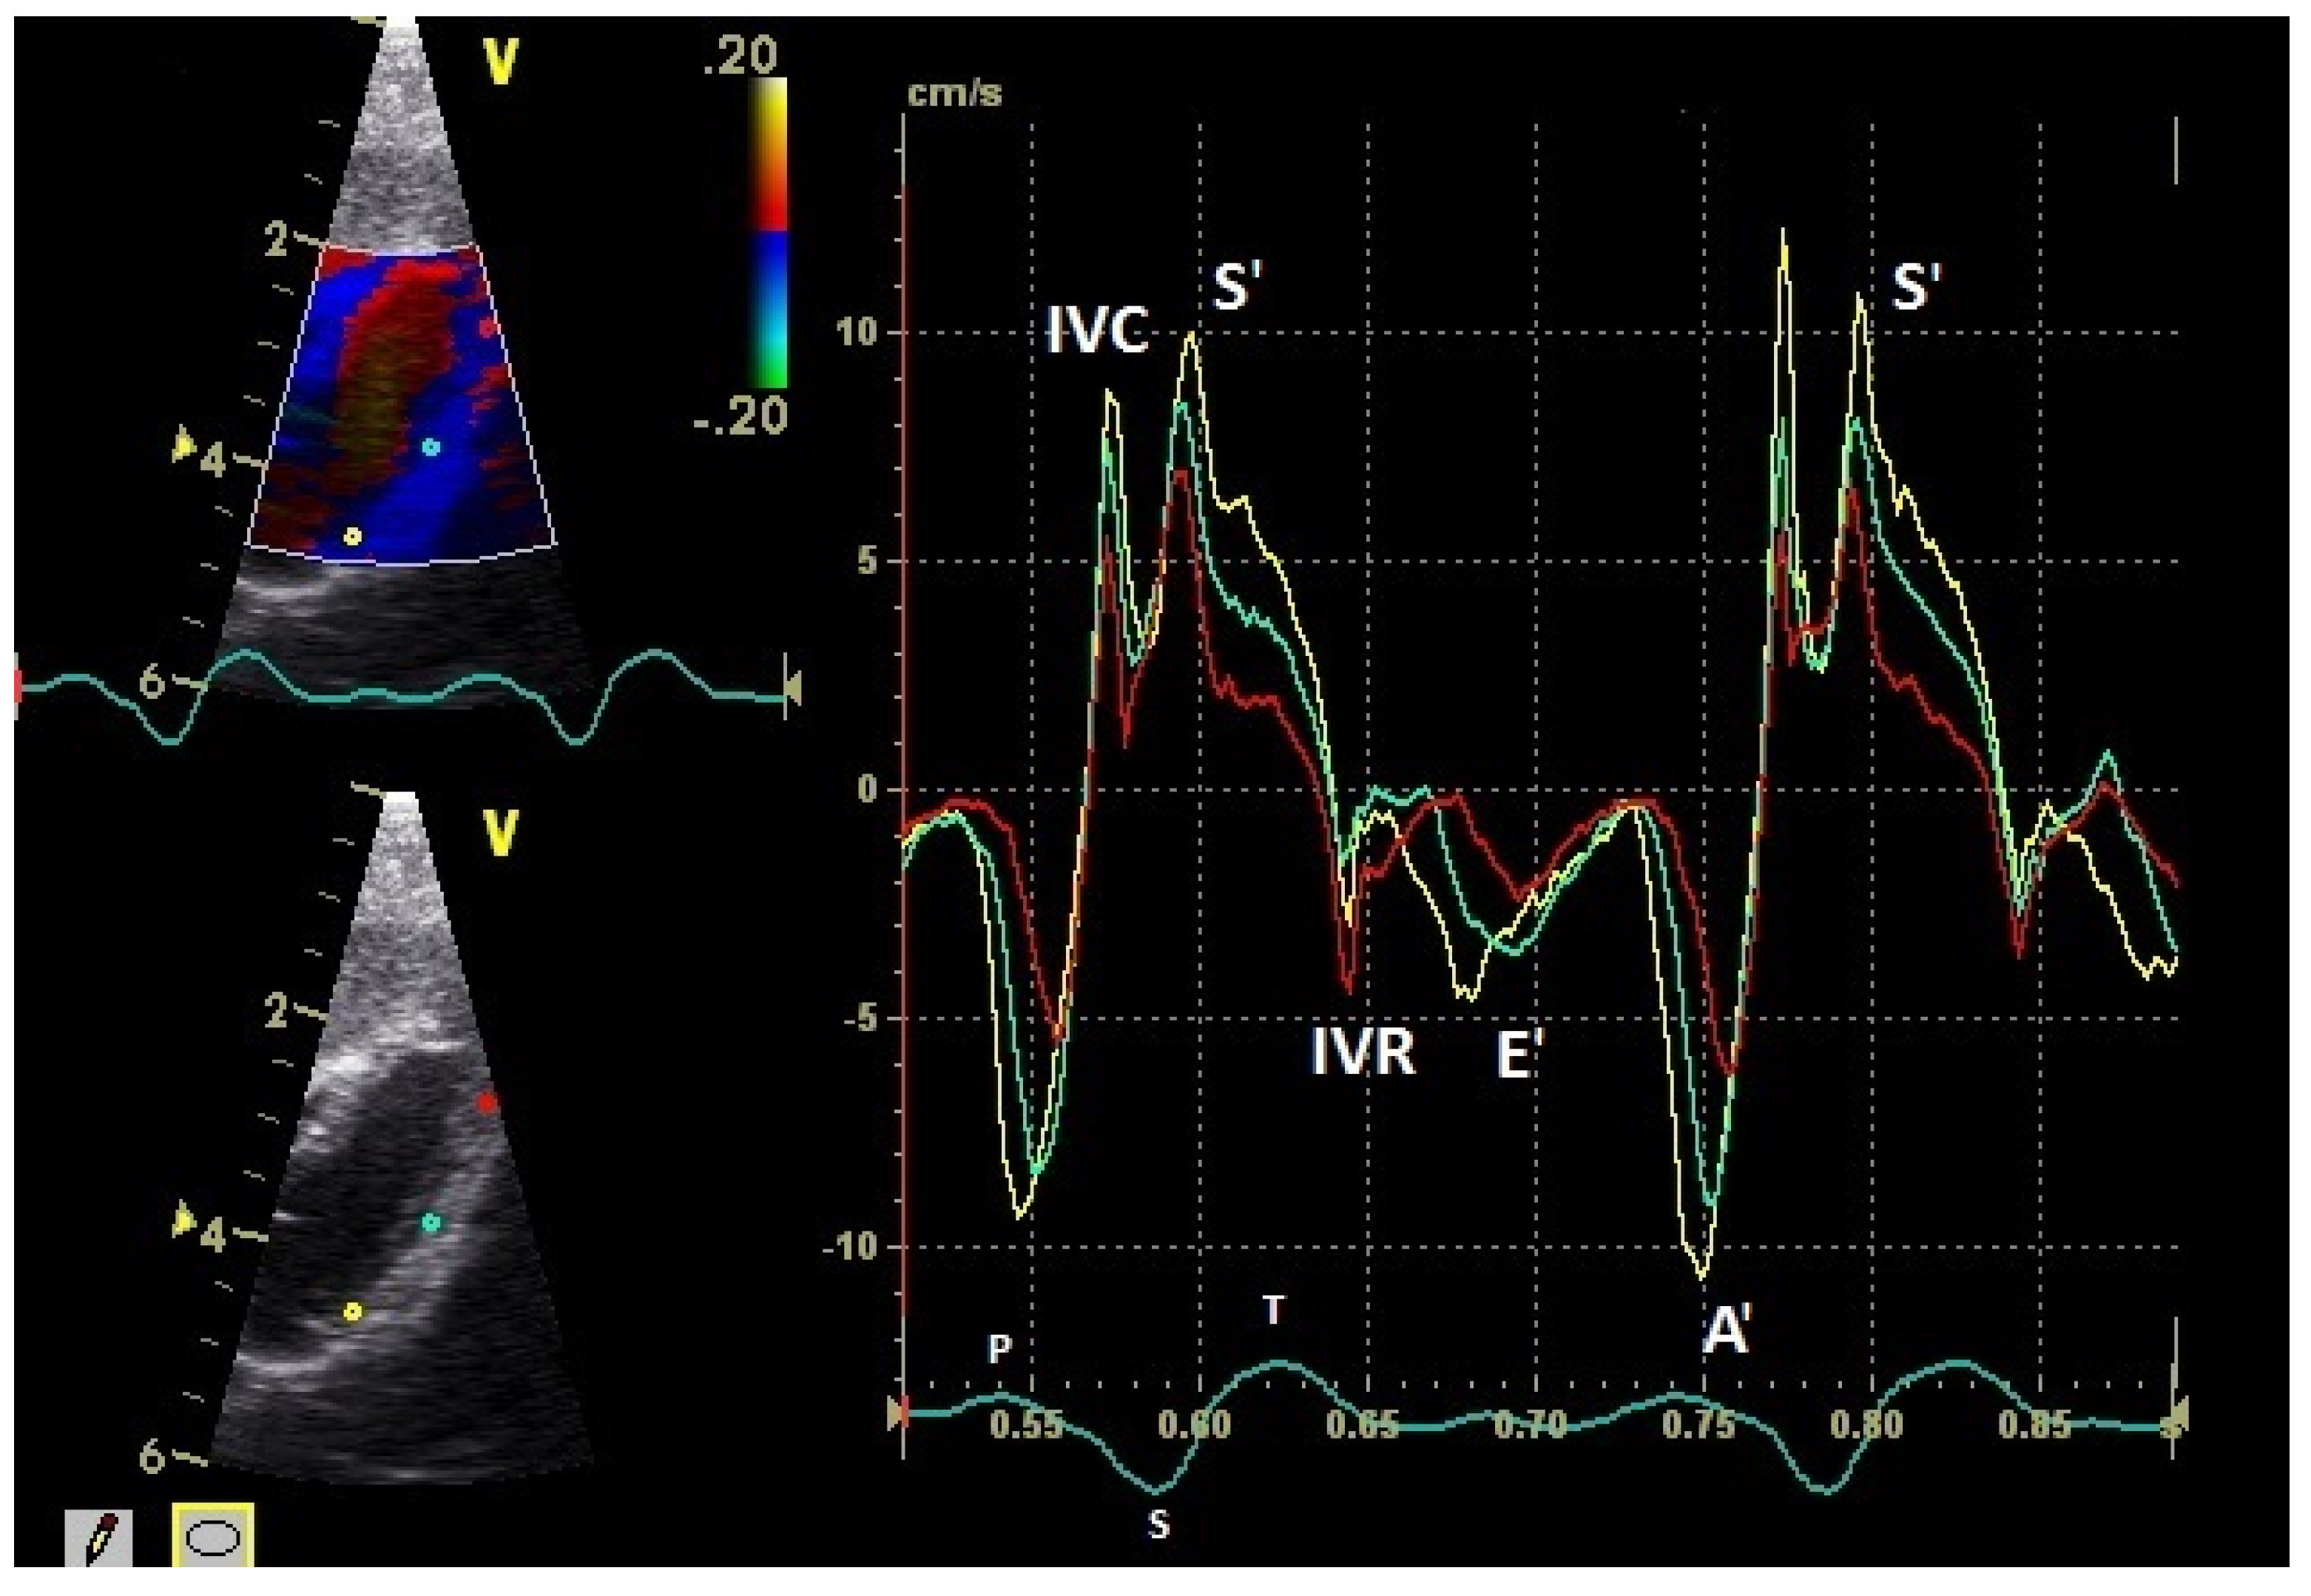

The positive S’ wave of the TDI curve (Figure 3 and Figure 4; ascending part of the S wave to the descending part of the T wave of the ECG) describes the systolic movement of the heart base toward the heart apex and represents the expulsion phase of the heart. In the middle of the S’ wave of the TDI, there is little movement of the heart apex toward the heart base and the myocardial velocities are negative (Figure 2). This movement in the middle part of the systole led to an irregular shape of the S’ wave in the TDI curve (Figure 3). The negative E’ wave (Figure 3 and Figure 4; after the T wave of the ECG) in the TDI curve describes the movement of the myocardium during the passive ventricular filling and the second negative A’ wave of the TDI curve (Figure 3 and Figure 4; P wave of the ECG) describes the movement of the myocardium in the active filling phases of the heart during the diastole away from the heart apex. Before and after the S’ wave, the TDI curve showed undirected deflections as a sign of isovolumetric contraction (IVC) and relaxation (IVR; Figure 3 and Figure 4). However, the transition between the A’ and S’ waves (IVC) and the S’ and E’ waves (IVR) could be flowing and sometimes difficult to see.

Figure 4.

Myocardial velocities of the left ventricular free wall in the four-chamber view measured by TDI (sample areas: Ø 2 mm). The tissue velocities of the basal (yellow), middle (green), and apical (red) segment are shown: early diastolic: E’ wave; late diastolic: A’ wave; systolic tissue velocities: S’ wave. Isovolumetric contraction: IVC; isovolumetric relaxation: IVR; HR: heart rate. Electrocardiogram: P: P wave; S: S wave; T: T wave.

The systolic and diastolic peak tissue velocities depending on the myocardial segment are shown in Table 1. In general, the highest myocardial velocities are visible at the atrioventricular valvular annulus in the basal segments. The velocities decrease significantly and continuously to the apex of the heart for the S’, E’, and A’ waves (p ≤ 0.001). Significant differences in the myocardial velocities could also be detected between the heart septum and the left and right free wall (Table 1).

The diastolic E’ wave velocities (passive diastolic filling) of the left and right free wall were significantly higher than in the septum (p ≤ 0.001). There were no significant differences between the E’ wave velocities of the left and right free wall. The A’ wave velocities in all heart segments were higher than the E’ wave velocities (p ≤ 0.001). The peak A’ wave velocities of the right free wall were significantly higher than the velocities of the left free wall (p ≤ 0.02). The left and right free wall velocities were significantly higher than the velocities of the heart septum (p ≤ 0.001).